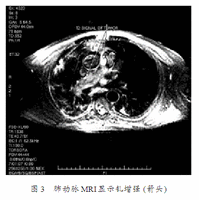

吸气性呼吸困难

吸气性呼吸困难,呼吸困难胸闷气短

吸气性呼吸困难 当声门变窄时,吸入的气流将声带推向下方,使两侧

2,声带息肉大者可以堵塞声门,引起吸气性喉喘呜和呼吸困难.

而引起吸气性呼吸困难的常见原因主要包括上呼吸道不全梗阻,肺水肿,肺